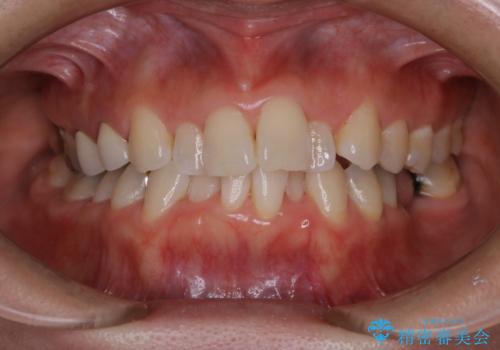

矯正治療の開始前にPMTCで汚れの除去

- これから矯正治療が開始される方です。装置の作成前にクリーニングを希望とのことでした。PMTC30分コースを行いました。

プラーク(細菌の塊)や歯石がたまると歯の表面はザラつきいてきます。そのザラつきは歯周病や虫歯菌の棲家となります。そのまま放置すると、歯肉が腫れてきたり、歯肉から出血したり、口臭が強くでたりします。とくに歯肉の境目は、歯磨きで汚れを除去することが難しく、プラーク(細菌の塊)や歯石が溜まりやすい場所です。

歯並が、がたついている場合はなおさら汚れが溜まりやすいです。矯正治療前や定期的にPMTCをすることで、矯正治療中の歯肉トラブルを防ぐことにつながります。